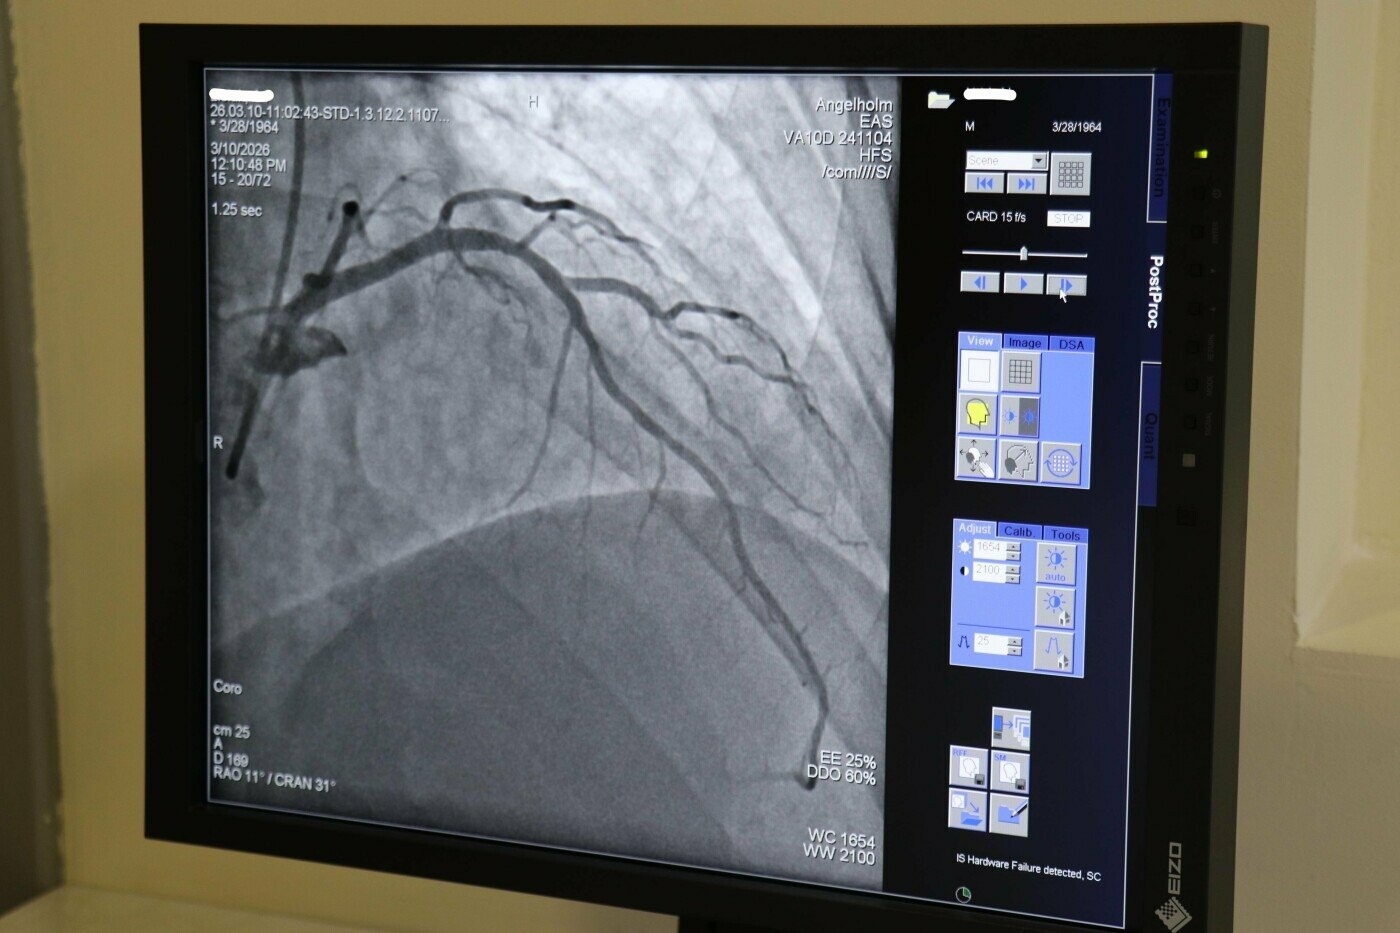

Ендоваскулярна хірургія — це сучасний метод лікування судинних захворювань через прокол у судині (зазвичай у руці або нозі) без відкритих операцій. Усі втручання проводяться під контролем ангіографа, що дозволяє лікарю бачити судини в режимі реального часу та максимально точно виконувати маніпуляції. Такий підхід значно зменшує травматичність, скорочує час операції та дозволяє пацієнту швидше повернутися до звичного життя.

- Коронарографія — діагностика стану судин серця для виявлення звужень та закупорок